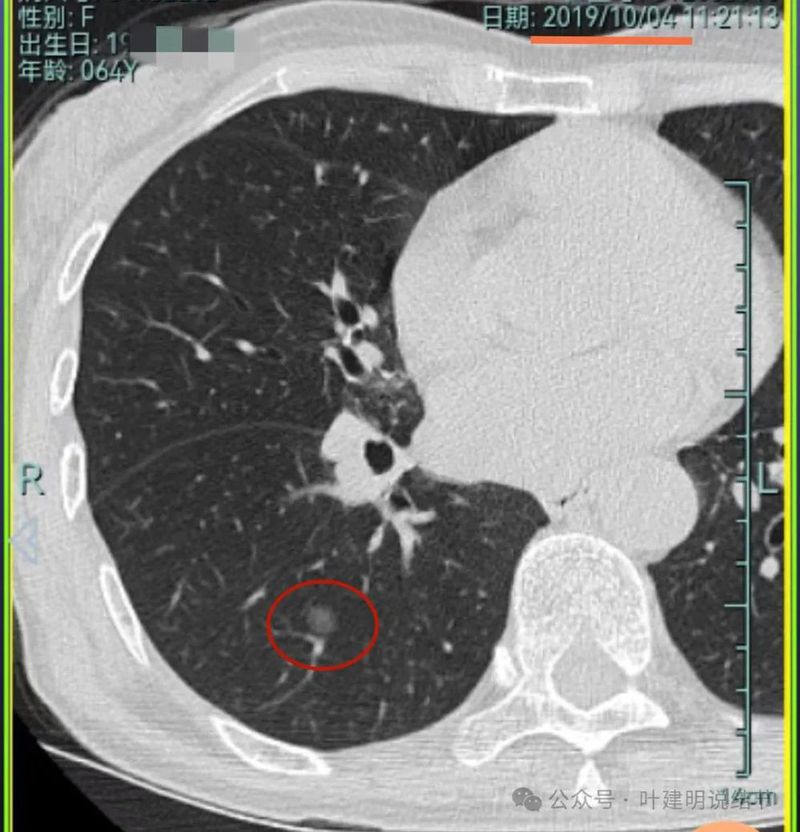

先来看2019年时的影像:

病灶3:右中叶混合密度结节,有分叶征,有收缩力,整体轮廓与边界清。

病灶4:右中叶伴钙化结节,考虑良性。

病灶5:右中叶磨玻璃病灶,轮廓与边界稍显模糊,灶内有支气管扩张的样子,贴叶间裂较近。